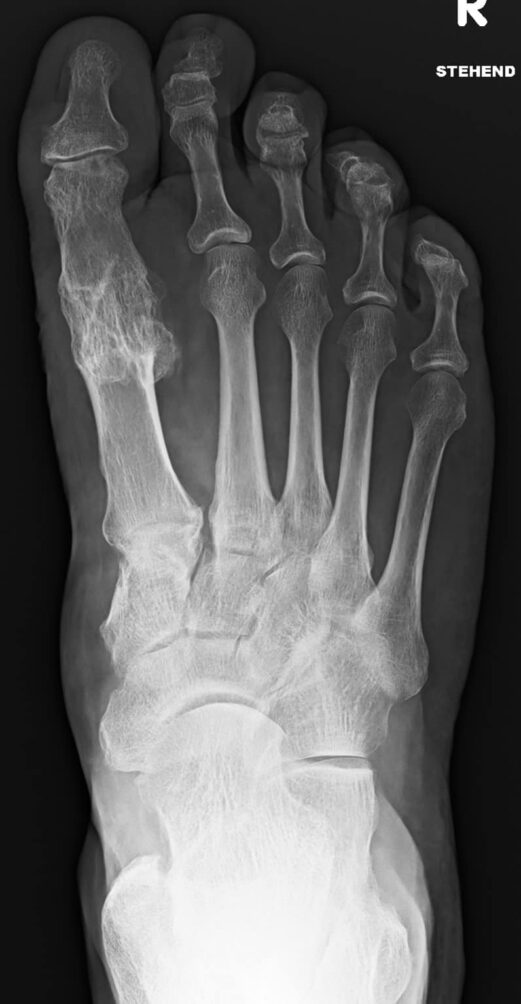

During production, the bone is first sterilized to ensure that no rejection reactions or disease transmission occur. A human bone matrix remains which is inserted into the human body in screw form. There it is immediately recognized as the body’s own – supplied with blood and integrated into the bone. After only six weeks, it has grown through with the body’s own tissue, and after approximately one year, it has healed completely into the patient’s bone and can no longer be seen in X-rays.

Patients who receive Shark Screw benefit from a maximum likelihood that the bone fragments will grow together and the bone screw will be converted into the patient’s own bone. This saves them the need for a second operation to remove the metal. Shark Screw can be used for fractures, deformities – such as hallux valgus – or joint wear or osteoarthritis.